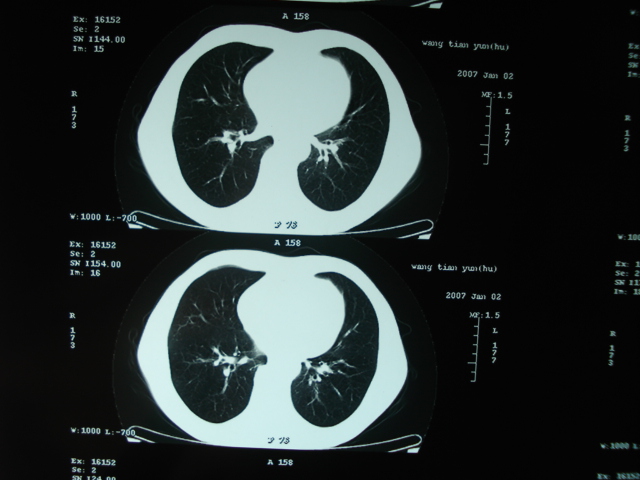

以下是引用狙击手在2007-4-18 20:17:00的发言:[br]原:2007/1/22号ct片:右肺上叶可见片状、云雾状高密度影,右肺上叶后段可见三角形高密度影,尖端指向肺门,右肺上叶后段支气管壁不规则增厚,管腔不规则增厚,纵隔未见肿大淋巴结.[br] 今ct:右肺上叶片状影增大,右肺上叶后段不张及右肺上叶后段支气管壁不规则增厚未见变化,右肺下叶背段支气管壁不规则增厚.[br] 如果考虑肺结核,但从临床证据看竟然没有一项支持肺结核,不知患者是否已经过正规抗结核治疗。没有的话,3个月了前后片看起来变化不大,似乎有不太符合肿瘤征象,不知患者是否抗炎治疗过,下叶支气管增粗还是要高度警惕,同意楼主意见,将常规病理,生化检查再做一遍。[br]

以下是引用狙击手在2007-4-18 20:17:00的发言:[br]原:2007/1/22号ct片:右肺上叶可见片状、云雾状高密度影,右肺上叶后段可见三角形高密度影,尖端指向肺门,右肺上叶后段支气管壁不规则增厚,管腔不规则增厚,纵隔未见肿大淋巴结.[br] 今ct:右肺上叶片状影增大,右肺上叶后段不张及右肺上叶后段支气管壁不规则增厚未见变化,右肺下叶背段支气管壁不规则增厚.[br] 如果考虑肺结核,但从临床证据看竟然没有一项支持肺结核,不知患者是否已经过正规抗结核治疗。没有的话,3个月了前后片看起来变化不大,似乎有不太符合肿瘤征象,不知患者是否抗炎治疗过,下叶支气管增粗还是要高度警惕,同意楼主意见,将常规病理,生化检查在做一遍。[br]